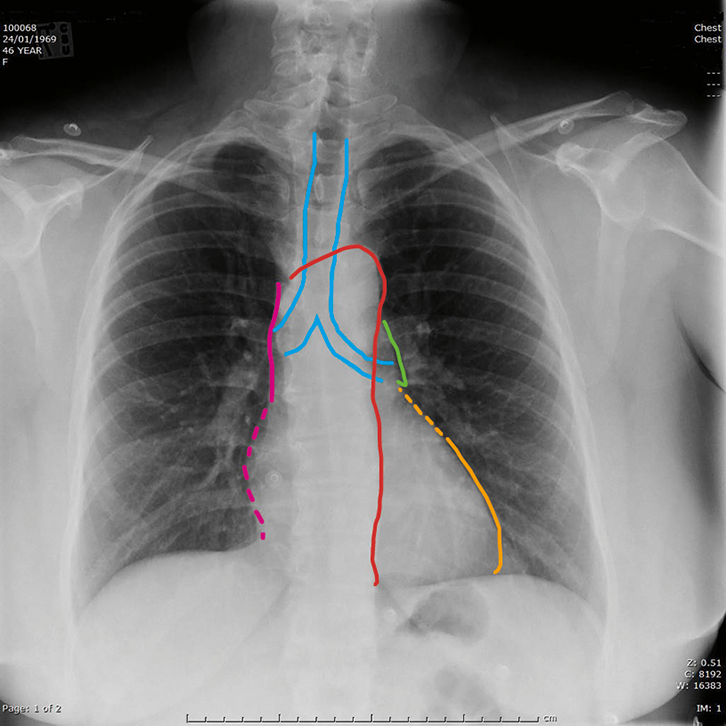

An urgent care chest X-ray is used to identify abnormalities or diseases involving the airways bones heart lungs and blood vessels in the chest. X-rays are made by using external radiation to produce images of the body its. Local Immediate Care Clinic Immediate Care Immediate Care Clinic Urgent Care.